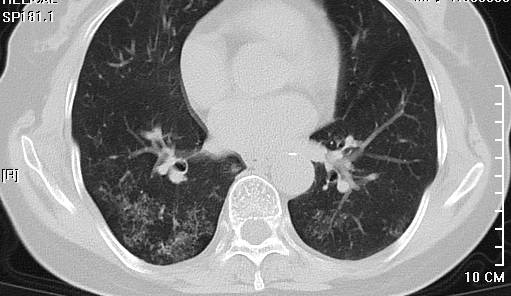

该病人在我院通过颅脑磁共振增强检查出左侧大脑镰旁占位性病变,来我院要求手术治疗,在完善相关术前检查时,患者的胸部CT结果却给我们带来诸多疑惑。

看到这样的胸部CT结果,神经外科医师做的第一件事就是再次核查患者流行病学史,反复确认新冠肺炎检查报告均为阴性后再请呼吸科、感染科医师会诊,会诊结合患者胸部CT均有考虑粟粒状肺结核灶可能,但患者入院后血常规、生化、血沉、痰找抗酸杆菌检查正常,结核分支核酸检测弱阳性。

会诊中,各科主任认真阅片并分析交流,在管床医师汇报完患者相关病史后,各个学科主任相继就本科专业导向做出发言,就患者是非需要术前抗结核治疗、肺部情况是否耐受手术等做出讨论,讨论中调阅2年前患者既往我院就诊的肺部影像资料,对比本次胸部CT无明显变化,最终讨论决定积极手术治疗并做好应急预案。